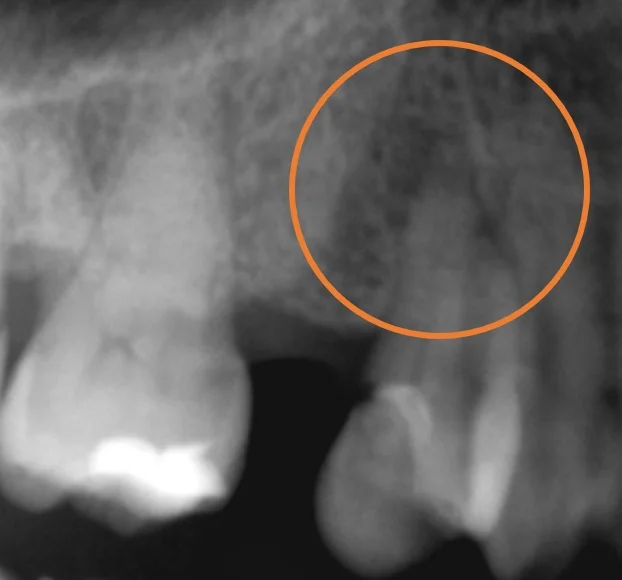

術前のレントゲンです。

若干、根尖(根の先)が黒くなっており、膿が溜まっているように見えます。

また、詰めたものと歯の間に大きなギャップがあり、その中で虫歯が進んでいます。